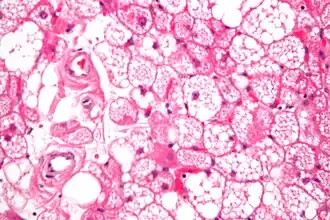

Coupe histologique d'un hibernome en coloration H&E

On distingue quatre types histologiques d'hibernome : typique, myxoïde, lipome-like et à cellules fusiformes[1],[2].